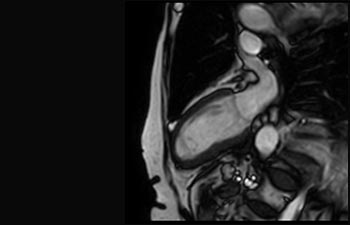

Acute myocardial infarction